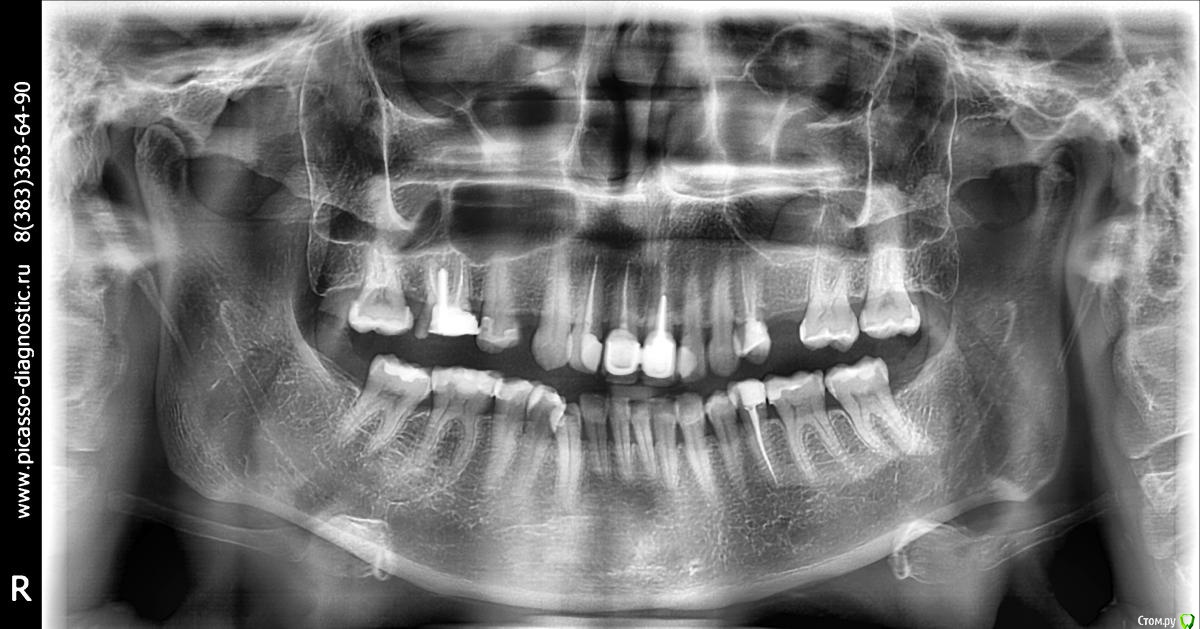

faity Опубликовано 24 апреля, 2017 Поделиться Опубликовано 24 апреля, 2017 Здравствйте, врачам не хватает объективных данных, прикрепите ОПТГ пожалуйста Ссылка на комментарий

k1mjke Опубликовано 3 мая, 2017 Автор Поделиться Опубликовано 3 мая, 2017 (изменено) Прошу прощения за долгое молчание, восстанавливала последний снимок. Прикрепила к сообщению. Изменено 3 мая, 2017 пользователем k1mjke Ссылка на комментарий

faity Опубликовано 3 мая, 2017 Поделиться Опубликовано 3 мая, 2017 По КТ: Брекеты, каппой уже проблему не решить, импланты, коронки Ссылка на комментарий